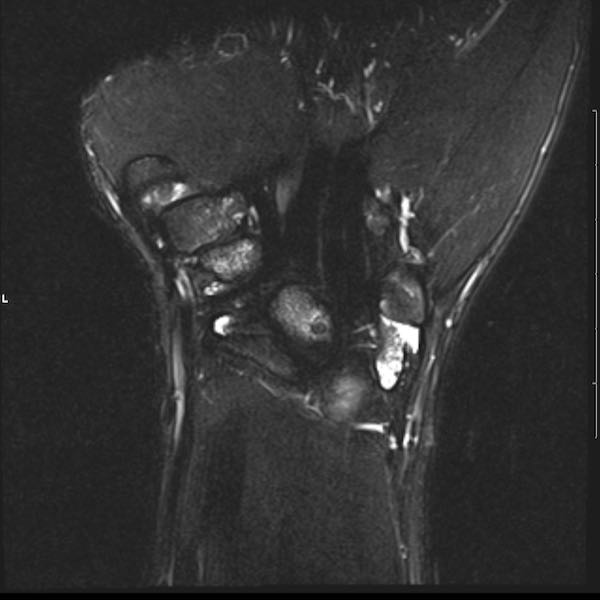

Tiếp tục xem hình ảnh MRI của bệnh nhân này.

Hình ảnh MRI:

Tràn dịch lan tỏa tất cả các khớp cổ tay.

Phù tủy xương lan tỏa tất cả các xương cổ tay.

Bào mòn xương, ví dụ tại xương thuyền, xương đầu và xương móc.

Phá hủy khe khớp và sụn khớp, rõ nhất tại khớp STT và CMC4/5.